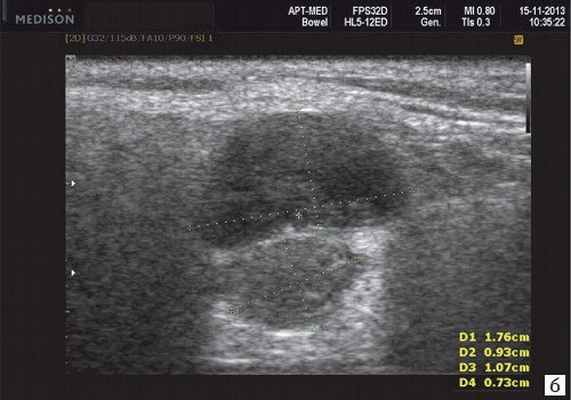

- обструктивные сиаладениты, развивающиеся при затруднении оттока слюны при обструкции выводного протока камнем (рис. 5-7) или сгустившимся секретом, а также вследствие рубцового стеноза протока. По распространенности процесса различают очаговый, диффузный сиаладениты и сиалодохит - воспаление выводного протока. Течение процесса может быть острым и хроническим;

Рис. 5. Камень протока поднижнечелюстной слюнной железы.

Рис. 6. Камень в паренхиме поднижнечелюстной слюнной железы.

Рис. 7. Камень в протоке поднижнечелюстной слюнной железы.